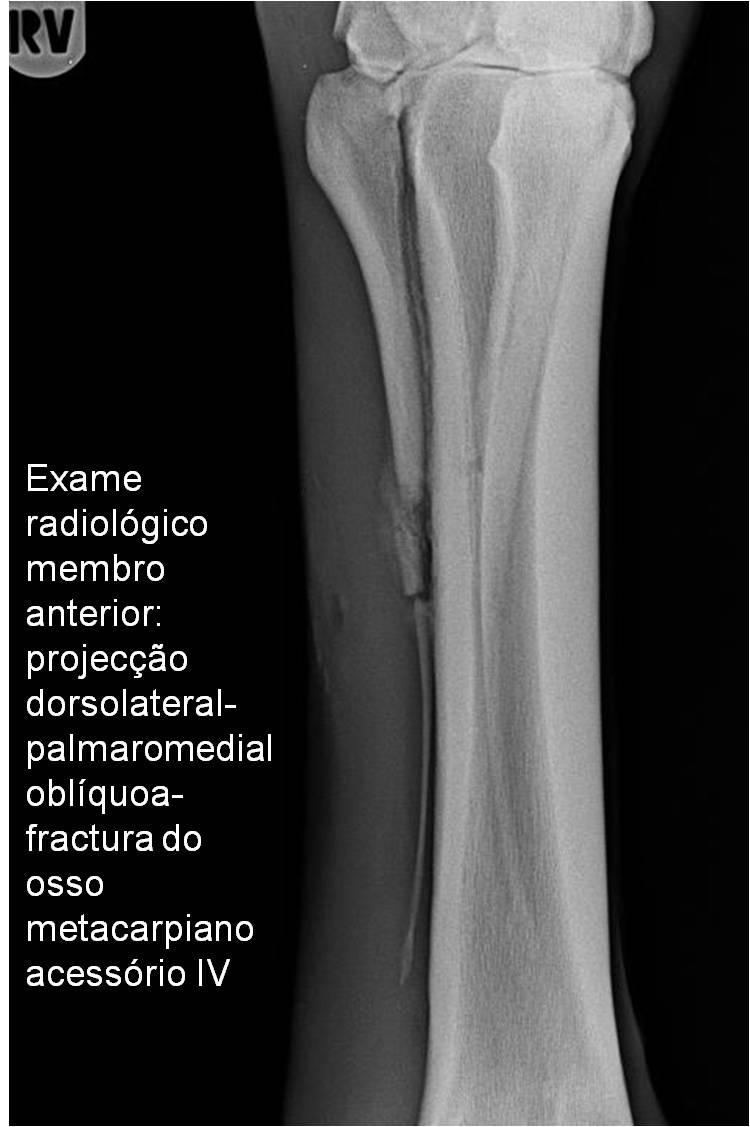

Publisher: Universidade de Évora

Abstract: O relatório de estágio encontra-se estruturado em três partes distintas. A primeira parte faz a caracterização das infraestruturas e funcionamento do Hospital Veterinário de Equinos de Lüsche, Oldenburg, Alemanha, assim como a análise casuística dos casos clínicos acompanhados durante os 6 meses de estágio. A segunda parte consiste de uma revisão bibliográfica sobre quistos do osso subcondral em equinos. Por fim, a terceira parte consta da apresentação e discussão de um caso clínico, nomeadamente o diagnóstico e acompanhamento imagiológico, por ressonância magnética, de um quisto subcondral na terceira falange num cavalo adulto; ### Abstract Equine Practice- Subcondral bone cyst of the third phalanx This internship report is divided in three parts. The first part characterizes the infrastructure and function of the Equine Hospital Lüsche, Oldenburg, Germany, as well as the casuistic of the clinical cases accompanied during the 6 month internship. The second part consists in a bibliographic review of cystic lesions of the subchondral bone in equines. The third part consists in a case report, the diagnostic and imagiological accompaniment, by use of magnetic resonance imaging, of a subchondral bone cyst in the distal phalanx of an adult equine.